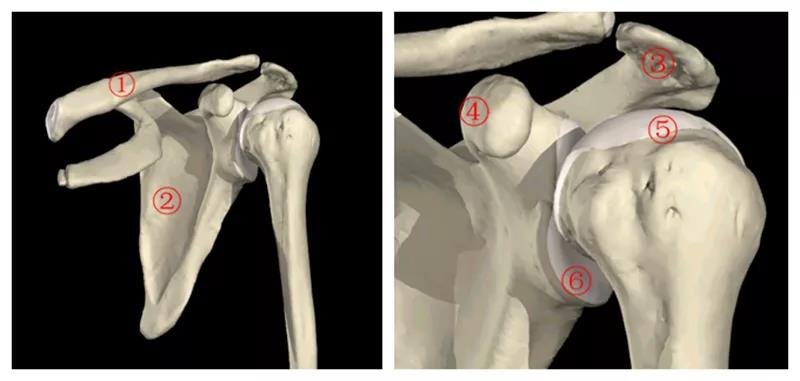

图1肩关节骨解剖 1.锁骨2.肩胛骨3.肩峰4.喙突5.肱骨头6.关节盂